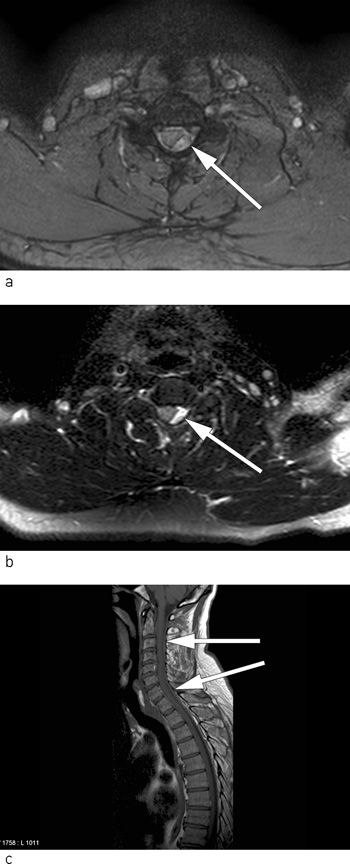

Etter trombolytisk behandling ble pasienten innlagt i Nevrologisk avdeling, og det ble planlagt en MR-undersøkelse av ryggmargen. På grunn av tidsvinduet for igangsetting av trombolytisk behandling ble ikke MR av ryggmargen utført i forkant. På avdelingen ble imidlertid paresene i høyre over- og underekstremitet verre, og det ble besluttet å utføre MR-undersøkelsen av ryggmargen akutt, samt ny MR av hjernen. MR av hjernen var fortsatt normal, men MR av ryggmargen viste en oppfylling forenlig med epiduralt hematom beliggende dorsalt på venstre side fra 3. til 7. cervikale nivå. På bildene er ryggmargen betydelig komprimert i 4. og 5. cervikale nivå (figur 2 a-c).

Pasientens symptomer og kliniske funn ble fortsatt oppfattet som et klassisk spinalis anterior-syndrom, og hematomet som ble oppdaget på MR-bildene ble antatt å være årsaken (11). Syndromet presenterer seg klinisk ved akutt tetra- eller paraparese, nedsatt smerte- og temperatursans, rectum- og blæreparese, men bevart vibrasjons- og leddsans. Spinalis anterior-syndromet skyldes okklusjon eller avklemming av a. spinalis anterior eller grener av denne (4, 10, 12).